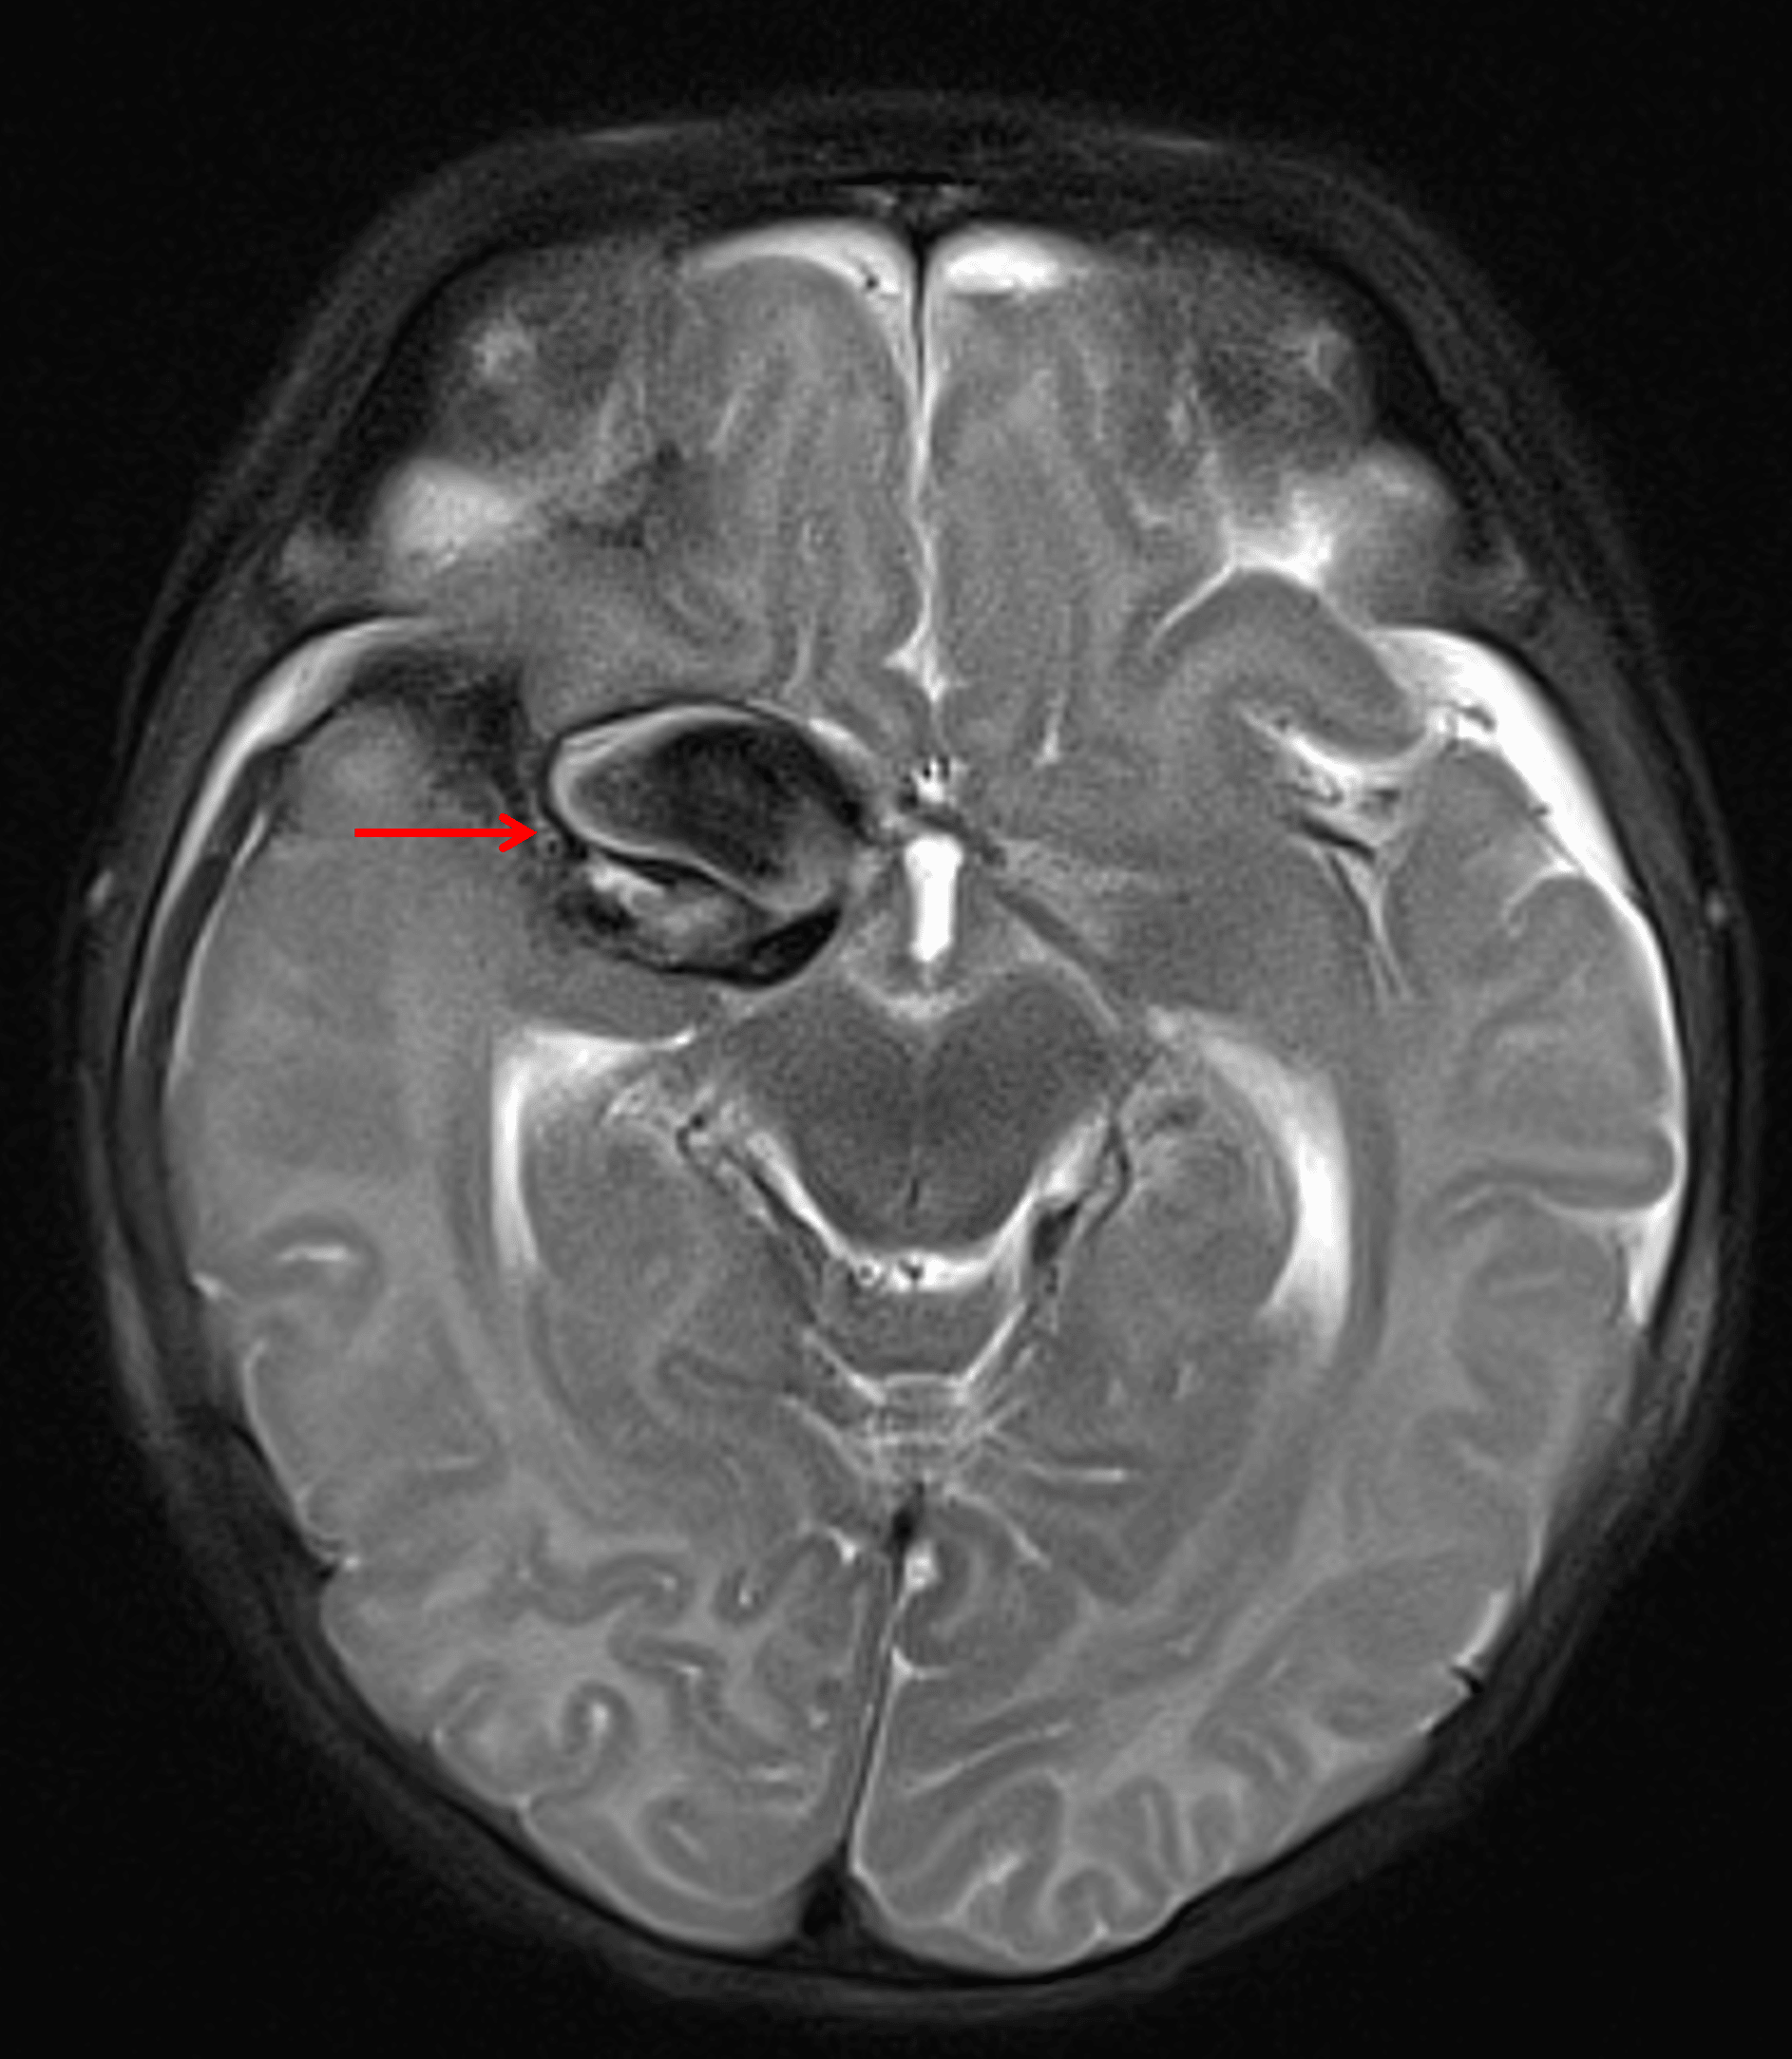

MRI

- Giant aneurysm involving the right internal carotid artery terminus and M1 segment of the right MCA with saccular component measuring 2.7 x 1.2 x 1.7 cm

- Radiating pulsation artifact

Corresponding markedly hypointense T2 signal with a swirling internal configuration (red arrow).